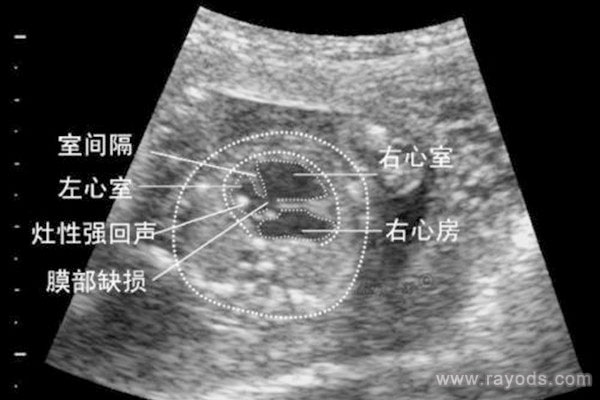

联体婴儿,这种情况为单卵双胎所特有的畸形。通过B超可以检查出来,如果孕期确诊后,建议及时做终止妊娠处理,这样对身体伤害会少很多。